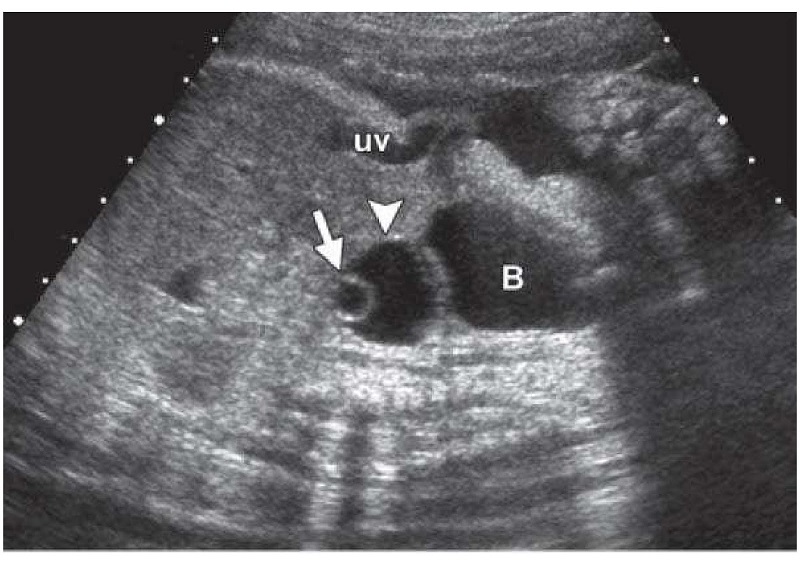

Nang trống âm buồng trứng một căn bệnh phụ khoa ở nữ với những dấu hiệu không rõ ràng, căn bệnh này được phát hiện khi siêu âm. Ngoài tên gọi là nang trống âm thì cách gọi khác là khối echo. Sở dĩ có tên gọi như vậy vì trong quá trình siêu âm, có một vùng hay một khối nào đó sẽ dội tiếng vang lại. Để dễ hình dung hơn, thì nang trống âm buồng trứng là hiện tượng có âm thanh vang lại trong quá trình buồng trứng siêu âm.

Siêu âm thấy nang trống âm buồng trứng phần nào cũng sẽ đưa đến những chẩn đoán ban đầu của căn bệnh u nang buồng trứng, vì với các bác sĩ chuyên môn thì nang trống âm là biểu hiện sơ khởi của căn bệnh này. Tuy nhiên, không phải bất cứ nang trống âm nào cũng sẽ dẫn đến khối u và sẽ phải dựa sự phát triển về sau của buồng trứng để đưa đến kết luận chính xác nhất. Nang buồng trứng có thể nằm ở 1 bên hay cả 2 bên của buồng trứng, thường thì xuất hiện phía bên phải.

Cấu trúc bên trong của các nang trống âm sẽ phụ thuộc vào mức độ dày hay mỏng của buồng trứng, nếu dày thì sẽ chứa nhiều loại tế bào như tóc, gân, móng hoặc bã đậu, nếu mỏng thì thường chỉ chứa dịch. Sẽ có nhiều dạng nang trống âm khác nhau được thể hiện qua các thuật ngữ của siêu âm, thường thấy như echo hỗn hợp, echo kém, echo trống…